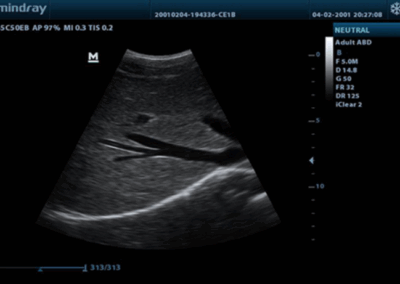

Z60

Sistema de diagnóstico ecográfico.

El sistema Z60 es una buena opción para aquellos que requieren un rendimiento de imagen de alta calidad, una movilidad simple y asequibilidad cuando se trata de imágenes ecográficas avanzadas. Con configuraciones completas y un diseño integrado, el Z60 es el resultado de los esfuerzos continuos y decididos de Mindray para hacer que la atención médica primaria sea más eficiente, eficaz y accesible para todos.